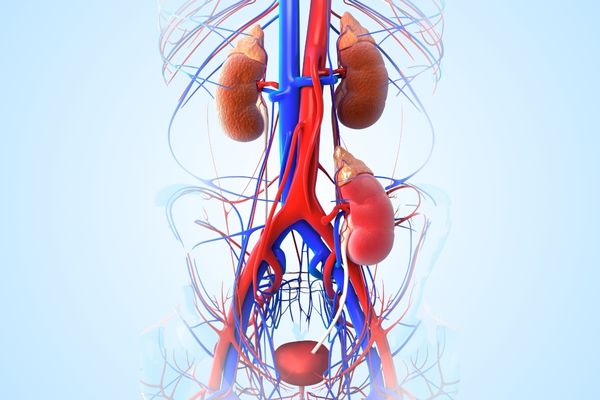

Kidney Stone Removed with Laser RIRS – No Cuts, No Pain

A large kidney stone was treated using advanced Laser RIRS by Dr. Omang Agrawal. The procedure was completely scarless with no external cuts, and the patient was discharged the next day without any complications.

Giant Ureteric Stone Removal

Complex Ureteric Stone Cleared

A challenging upper ureteric stone near the spine was removed using laser surgery. The patient was discharged the next day without any complications and with fully restored kidney function.

Expert Care for Pediatric Kidney & Ureter Stones

Successfully treated a 5-year-old child for a kidney/ureteric stone with a safe and effective stone removal procedure. The child is now pain-free and going home the very next day! 🏥💪

At Ram Kishori Urology & Gynecology Clinic, we specialize in gentle, child-friendly urological care, using advanced techniques to ensure quick recovery and minimal discomfort — even in our youngest patients.